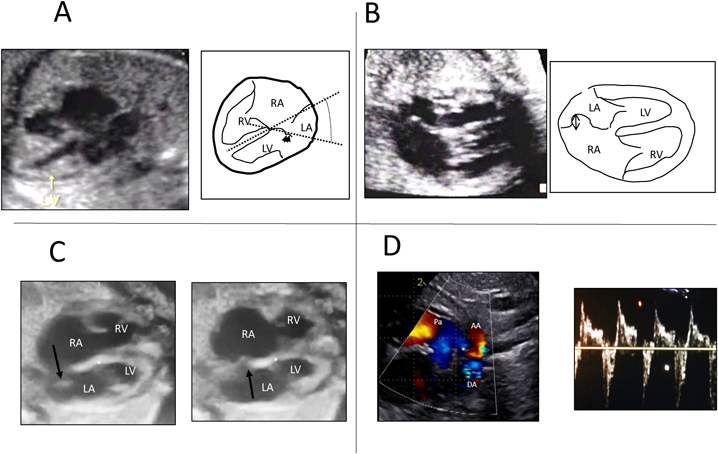

8. 完全大血管転位(complete transposition of the great arteries: TGA)

TGAは四腔断面が正常であるため胎児診断の難しい疾患とされていたが,近年スクリーニング方法(I-shaped sign17)など)の開発などから診断例が増加している.診断された場合にはVSDとPSの有無による病型分類を行い,1型の場合には卵円孔狭小化・閉鎖の有無の確認および動脈管狭小化の有無の確認が出生後の状態評価のためには重要である.具体的には,Maenoらの呈示した胎児卵円孔の異常として「Fixed, flat, redundant」18)やPunnらの「Hypermobile septum, reverse diastolic DA shunt」19)がある.いずれも出生後の重度チアノーゼ,緊急BASの必要性を予想するのに有用とされている.それらの画像をいくつか示した(Fig. 6).